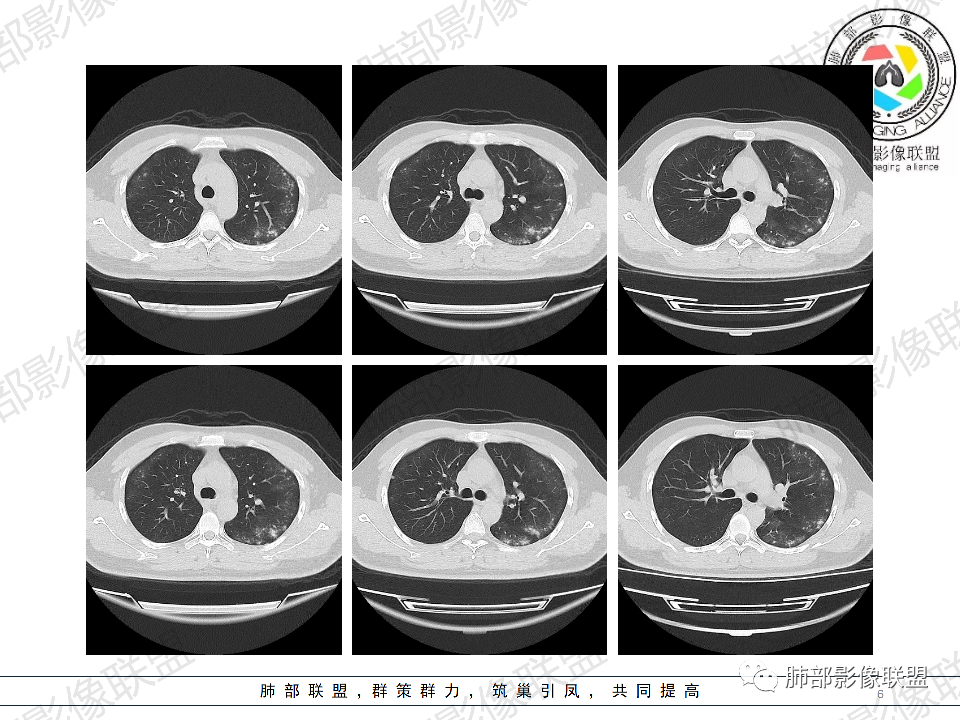

年轻男性,有HIV病史,免疫力缺陷病史,CD4明显减低,左肺胸膜下多发大小不等结节影,部分侧向融合,平行于胸膜,周围伴有模糊的GGO,部分结节与血管相连,血管束增粗,考虑隐球菌,建议查隐球菌荚膜实验,脑脊液隐球菌荚膜,鉴别:CMV(局限性比较少见)

年轻人,男性,HIV阳性,双肺多发斑片状,结节状阴影,以胸膜下分布为主,病灶与支气管血管束垂直生长,周围可见磨玻璃影,考虑肉芽肿病变,隐球菌感染可能性大,鉴别GPA,胞子菌肺炎。

双肺胸膜下多发大小不等结节伴晕征,部分似有融合

左肺多发大小不等结节影,部分融合,胸膜下分布为主,平行于胸膜,周围伴有磨玻璃晕,考虑隐球菌,鉴别:PJP

年轻男性,HIV阳性,胸闷喘憋,双肺胸膜下多发斑片结节影,周围伴晕,部分融合,白细胞低,CD4明显减低,考虑机会性感染性病变,隐球>PCP>结核

青年男性,HIV阳性,白细胞及淋巴细胞显著降低,CRP增高,胸闷气喘一周,影像为双肺胸膜下平行于胸膜分布的多发大小不等结节伴晕,单从影像上看,隐球是要首先考虑,但是不好解释临床症状。需要鉴别:1、曲霉所致IPA,临床有粒缺基础,胸闷一周要考虑,但影像不是典型的血道或气道分布又存疑,2、马尼,CD4低,HIV基础,要考虑,但是否有旅广史?另外纵隔淋巴结无肿大,肝脾不肿大,可能稍小。3、PCP,HIV基础,CD4低,胸闷气喘要考虑,影像分布不典型。4、腺病毒或EB病毒感染,HIV基础,影像改变要考虑,但是发病无发热,存疑。5、结核,临床与影像均不典型。可能小。综上,隐球>曲霉>PCP>马尼>病毒感染。下一步,查隐球荚膜抗原,NGS找病原体。

我们科里读片的时候,也是觉得主诉特别像PCP的主诉。但是影像学表现,双肺胸膜下多发小结节,结节周围带晕,蘑菇兄弟手拉手,有的结节侧向融合整体与胸膜平行。影像符合隐球。我们科里艾滋合并隐球菌真正确诊出来的很少。所以要说总结HIV合并隐球的病例特点,我没有发言权

肺隐球菌多分布在肺野外带或胸膜下区域,下叶多见,可能余隐球菌更容易在胸膜下肺泡中定植或蔓延有关;显示腺泡结节,然后取决于宿主免疫,可以入血,然后血播

如果是血播是随机分布,他这个是胸膜下

不是血道,就是直接吸入到远端肺泡

隐球结节的实质隐球菌自气道来,然后在支气管远端(呼吸性细支气管及肺泡)以及肺实质形成炎性肉芽肿结节

2、类型:常见有孤立肉芽肿型、肺炎实变型、混合型(多发结节/实变/空洞)、弥漫粟粒/间质型。免疫正常宿主多表现为孤立肉芽肿型,也可以表现为肺炎实变型或混合型。免疫缺陷宿主则容易肺内播散形成多发(结节、实变、空洞)或弥漫粟粒/间质型,可累及中枢系统并发隐球菌脑炎。

5、分布:病灶分布多位于胸膜下,可紧贴胸膜,也可与胸膜邻近,病灶长轴与胸膜平行。(划重点,分布特点非常重要)

8、晕征:病变早期可出现磨玻璃晕征,为周围炎性渗出或肺间质受累。

9、坏死:可无坏死,也可凝固性坏死,出现空洞,空洞可规则光整呈类圆形,也可以为不规则厚壁,或出现“鬼脸征”。

10、“葫芦兄弟”:邻近胸膜多发结节,形态密度类似,可簇状分布,较少多形性,没有新旧不等。

12、少见征象:少见胸水、树芽征、液化坏死、明显钙化、空气新月征、腺泡结节。